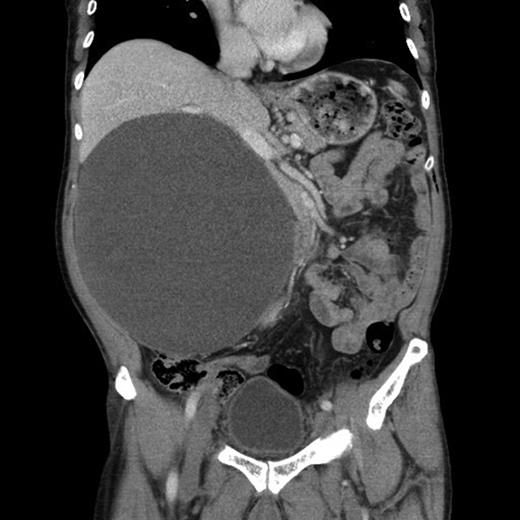

The CT (Figs 1–3) was performed identifying a unilocular, cystic lesion arising from within the right side of the abdomen. This lesion was distinct and not found to be related to any of the intra-abdominal organs. The radiological dimensions of the lesion were 22 × 20 × 19 cm. There were no radiological features to suggest acute or chronic pancreatitis. The findings were explained to the patient, and he was booked for laparotomy and excision of the cyst.

Axial slice from the CT imaging identifying the retroperitoneal pseudocyst.